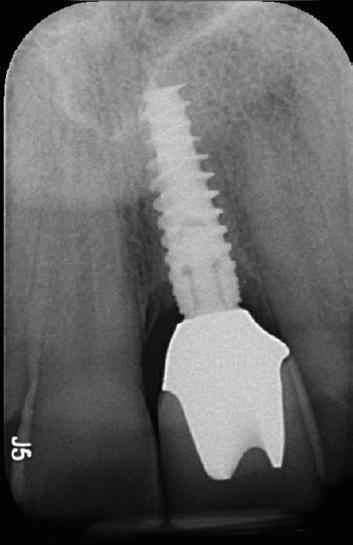

De asemenea, trebuie evaluate anual modificările radiografice. În ședința de inserție a restaurării, se înregistrează o radiografie bitewing standardizată pentru a permite evaluarea anuală a modificărilor osoase din jurul implantului. Remodelarea osului alveolar în primul an este bine documentată și depinde de tipul de implant utilizat; cu toate acestea, nu ar trebui să apară apical de primul filet al implantului. Prin urmare, este importantă abilitatea de a vizualiza filetele implantului pe radiografii. Modificările pierderii osoase de 2 mm sau mai mult după primul an reprezintă un semn de periimplantită. De îndată ce pierderea osoasă este recunoscută, pacientului trebuie să i se recomande terapia imediată pentru a opri procesul de boală.

RECONSTITUIREA țesuturilor moi periimplantare. Scopul acestui raport de caz este de a demonstra procedurile chirurgicale utilizate pentru corectarea unui defect al țesuturilor moi periimplantare folosind țesutul moale interdentar în combinație cu tuberozitatea ca locație donatoare de țesut conjunctiv, utilizând o abordare prin tunelizare într-o zonă estetică.